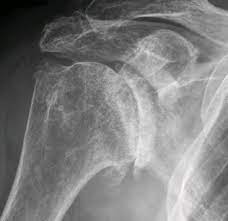

1. X-ray 검사 :

정형외과에 방문하시게되면 가장 많이 하시게 되시는 검사입니다. 가장 기본적이면서도 가장 먼저 감별해야할 위험한 진단을, 예를 들면 골절이나 골종양 등을 발견할 수 있게 해주는 값싸고도 고마운 검사입니다.

동결건에서 X-ray는 사실 진단에 큰 역할을 하기보다는, 그 기저 질환이 무엇인지 알아낼 수 있는 장치로써, 기본적으로 촬영하게 되는 검사입니다.

앞에서 말씀드린 이차성 동결건의 원인 중 하나인 석회성 건염이 있는지를 감별하게 해주며, 관절염이 심하게 진행되신 분들도, 단순 엑스레이 검사를 통해서 감별이 가능합니다.